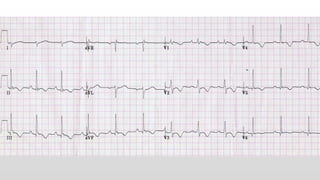

This document discusses various cases of collapse and syncope. It defines collapse as transient loss of consciousness with loss of postural tone and full recovery. Syncope is defined as loss of postural tone with or without loss of consciousness and full recovery. It then discusses the multiple potential causes of collapse and syncope including toxicological, cardiac conduction abnormalities, structural cardiac issues, autonomic dysfunction and more. It then goes through 9 case examples, discussing important questions to ask, potential tests and interventions for each case.